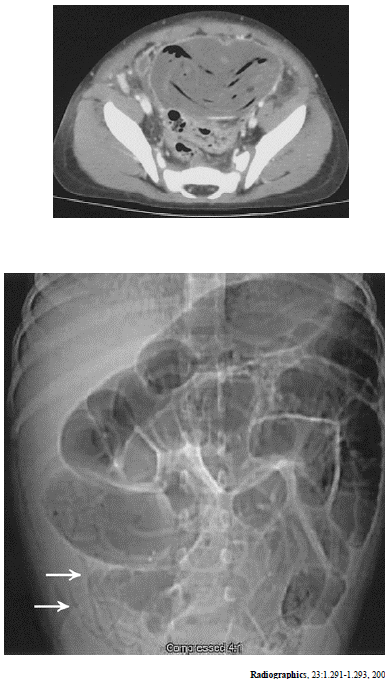

As imagens acima são de um mesmo paciente. Considerando essa imagens e os achados por elas revelados, julgue os itens subseqüentes.

As imagens acima são de um mesmo paciente. Considerando essa imagens e os achados por elas revelados, julgue os itens subseqüentes.

Existe grande dilatação do cólon sigmóide.

As imagens acima são de um mesmo paciente. Considerando essa imagens e os achados por elas revelados, julgue os itens subseqüentes.

As setas indicam a presença de parasitas.

As imagens acima são de um mesmo paciente. Considerando essa imagens e os achados por elas revelados, julgue os itens subseqüentes.

Há sinais de semioclusão intestinal.